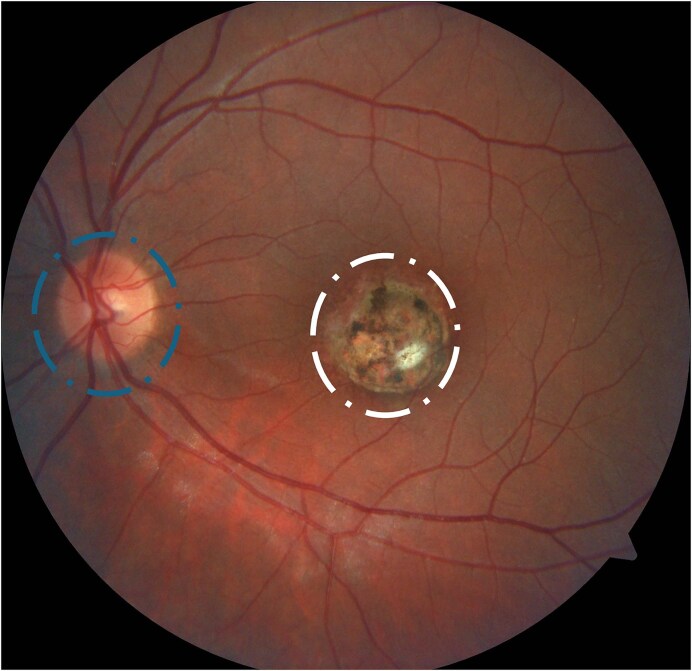

弓形虫病是一种寄生虫感染,对人类健康具有重大影响,特别是其眼部形式,可导致严重的视力损害。虽然基础和临床研究在了解这种寄生虫的生物学和治疗方面取得了相当大的进展,但挑战仍然存在。最近在诊断方面的进展,主要是通过多模态成像,改进了活动性疾病的识别和预测结果。实验性疗法也在不断涌现,为更有效的治疗提供了新的希望。然而,从最近的研究中,特别是在第17届国际弓形虫病大会上强调的最关键的见解是合作方法的必要性。整合基础和临床研究对于将分子和病理生理发现转化为有效的临床实践至关重要。这种协同作用对于推进治疗策略和改善眼弓形虫病患者的预后至关重要。

Toxoplasmosis is a parasitic infection with significant implications for human health, particularly in its ocular form, which can lead to severe visual impairment. While both basic and clinical research have made considerable strides in understanding the biology and treatment of this parasite, challenges remain. Recent advancements in diagnostics, mainly through multimodal imaging, have improved the identification of active disease and predicting outcomes. Experimental therapies are also emerging, offering new hope for more effective treatments. However, the most critical insight from recent research, particularly emphasized at the 17th International Congress on Toxoplasmosis, is the necessity of a collaborative approach. Integrating basic and clinical research is essential for translating molecular and pathophysiological findings into effective clinical practices. This synergy is crucial for advancing treatment strategies and improving patient outcomes in ocular toxoplasmosis.